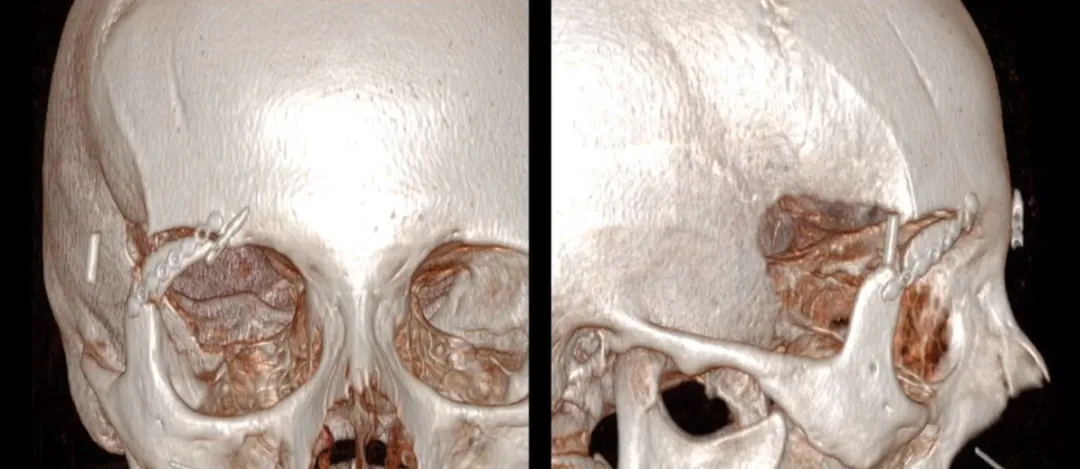

A:通过改良ETOA进行眶缘开颅术的示意图

B:完成解剖后的计算机断层扫描三维重建图